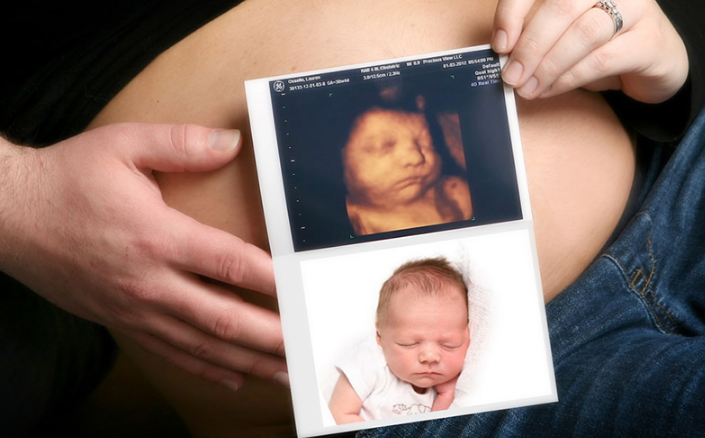

Khi thai 32 tuần, mẹ nên siêu âm 4D vì lúc này thai nhi đã đủ lớn, khi siêu âm, mẹ có thể nhìn rõ các bộ phận của cơ thể, đặc biệt khuôn mặt bé khá giống với lúc sinh.